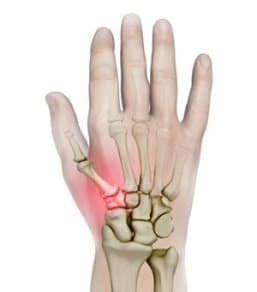

Wrist Scaphoid Fractures

Wrist Scaphoid Nonunion